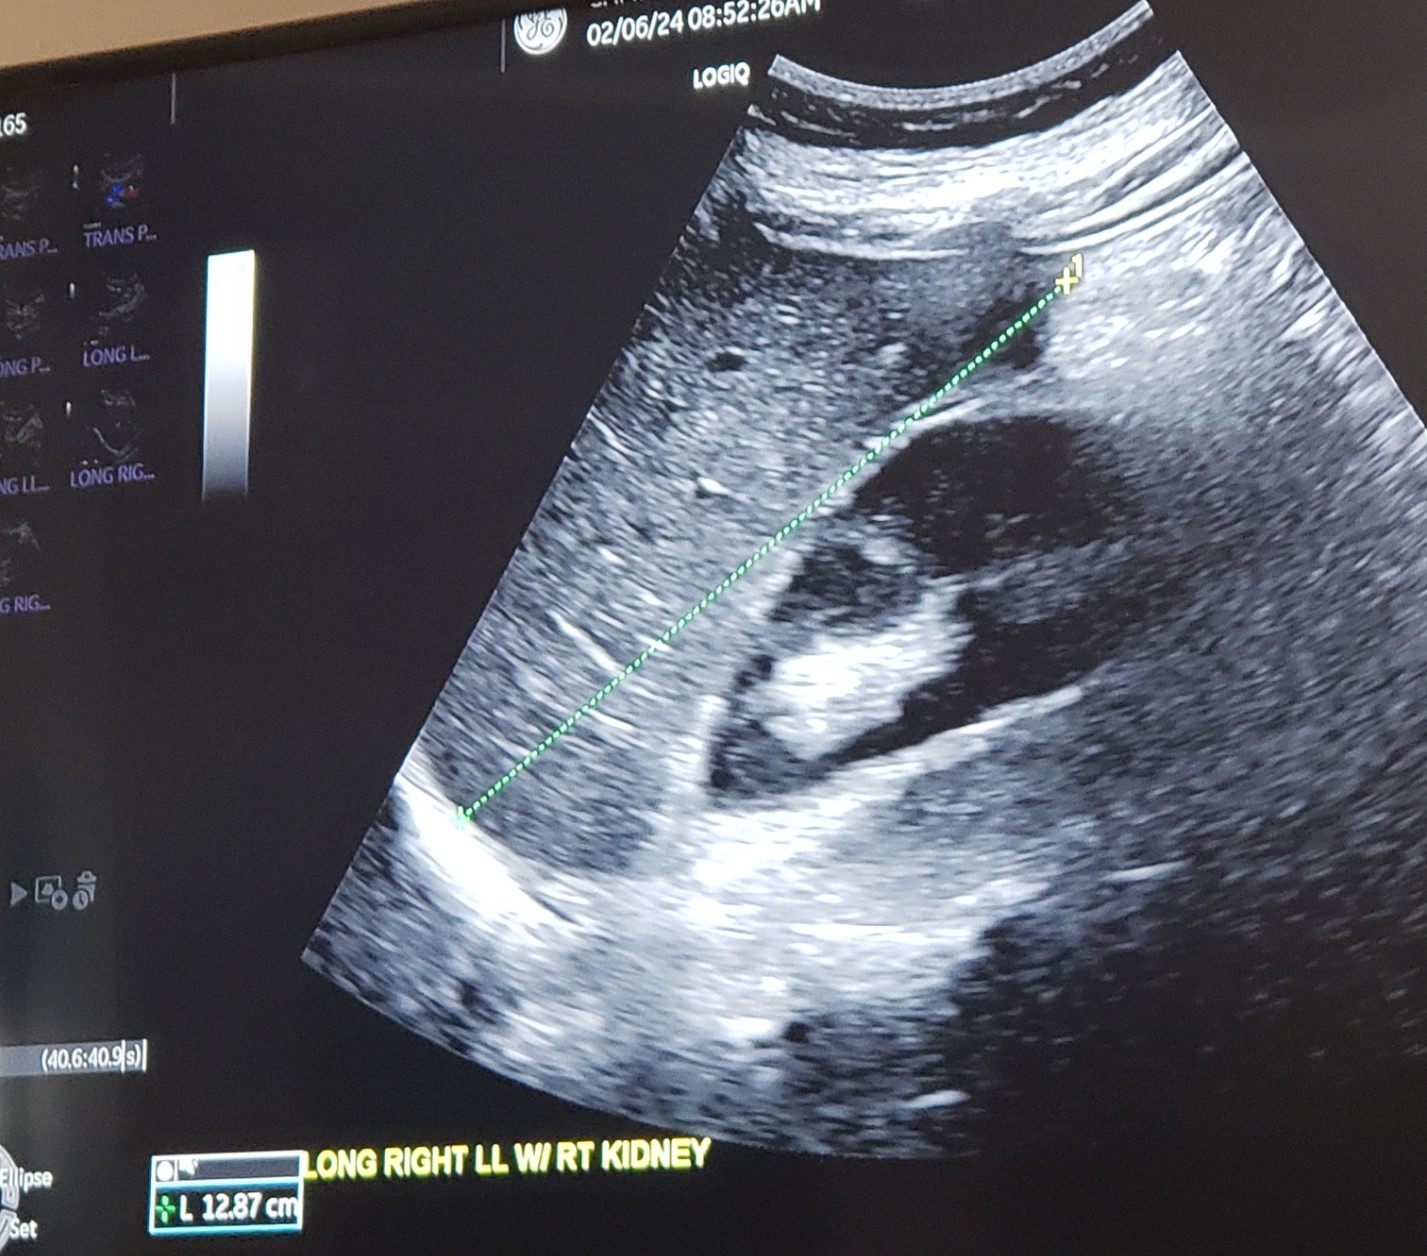

Sag./Long RLL w/ Rt. Kidney interface w/ measurement